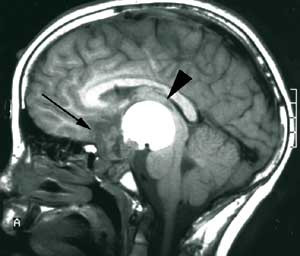

Pasient 2. Ni år gammel gutt med normal psykomotorisk utvikling frem til åtte års alder. Han utviklet da vekstretardasjon og det ble senere påvist en generell hormonsvikt og økende synstap. Radiologisk utredning viste en stor cystisk tumor i hypofyseregionen med affeksjon av synsbaner og hypothalamus. Tumor ble oppfattet som et kraniofaryngeom.

Det ble utført en stereotaktisk punksjon av cysten med instillasjon av radioaktivt yttrium. Man oppnådde imidlertid ikke tumorkontroll. Fire måneder senere utførte man derfor en kraniotomi og reseksjon av tumor. Under inngrepet viste det seg umulig å redde restsyn og hypofysefunksjon. Videre utviklet pasienten hydrocephalus postoperativt og fikk anlagt en ventrikuloperitoneal shunt.

I løpet av få måneder fikk gutten på nytt økende symptomer i form av hodepine, irritabilitet og personlighetsendringer. MR viste gjenvekst av tumor.

Pasienten ble henvist til Nevrokirurgisk avdeling, Rikshospitalet for vurdering med tanke på ytterligere kirurgi. Det forelå nå imidlertid en betydelig tumordestruksjon og invasjon i clivus av solide tumorkomponenter og ny cyste posterokaudalt mot 3. ventrikkel/hypothalamus og pons (fig 3a). Klinisk var pasienten også i meget rask forverring og hadde preoperativt redusert bevissthet, sløvet tale, ustø gange og urininkontinens.

Pasienten er ved tremånederskontroll betydelig restituert og har kun en mindre ekstremitetsparese. Som før den siste operasjonen er han blind og fullstendig hormonsubstituert. Postoperativ MR-undersøkelse viser ikke tegn til resttumor (fig 3b).